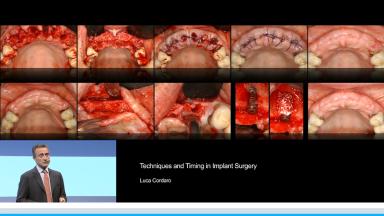

Techniques and Timing in Implant Surgery - Congress Lectures - Home

Techniques and Timing in Implant Surgery

Surgical procedures to place implants are a routine part of everyday work in most dental offices. The clinician has to choose among different options when it comes to flap access, drilling technique, timing of implant placement in relation to extraction, timing of the potential augmentation procedure and submerged versus non-submerged healing. These decisions are usually made depending on the dentist’s preference and/or clinical ability and not on the clinical scenario, as it should be. The aim of this lecture is to describe the indications and critical aspects of most surgical variables with particular attention to soft tissue aspects, the choice of the interval between extraction and implant placement, and the timing of the augmentation procedure.

At the end of this Congress Lecture you should be able to…

- describe the different implant placement protocols available

- evaluate the risks and advantages of different protocols for the timing of implant placement in relation to tooth extraction

- recognize the importance of preoperative planning for achieving the best possible treatment outcome while minimizing the risks of complications